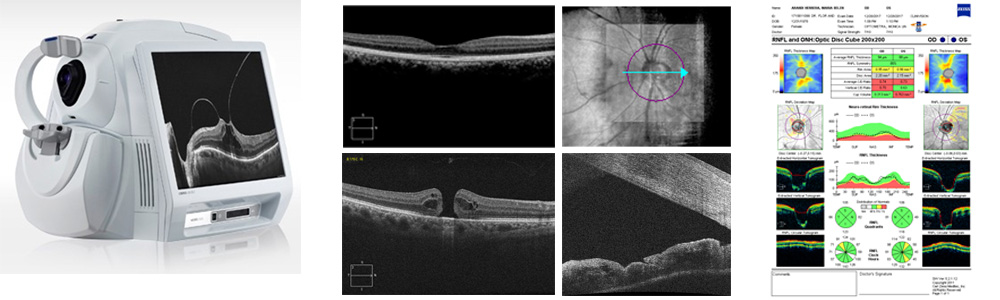

Tomografia optica coherente cirrus hd oct

EQUIPOS DE DIAGNÓSTICO OCULAR

Contamos con equipos de última generación y tecnología de punta.